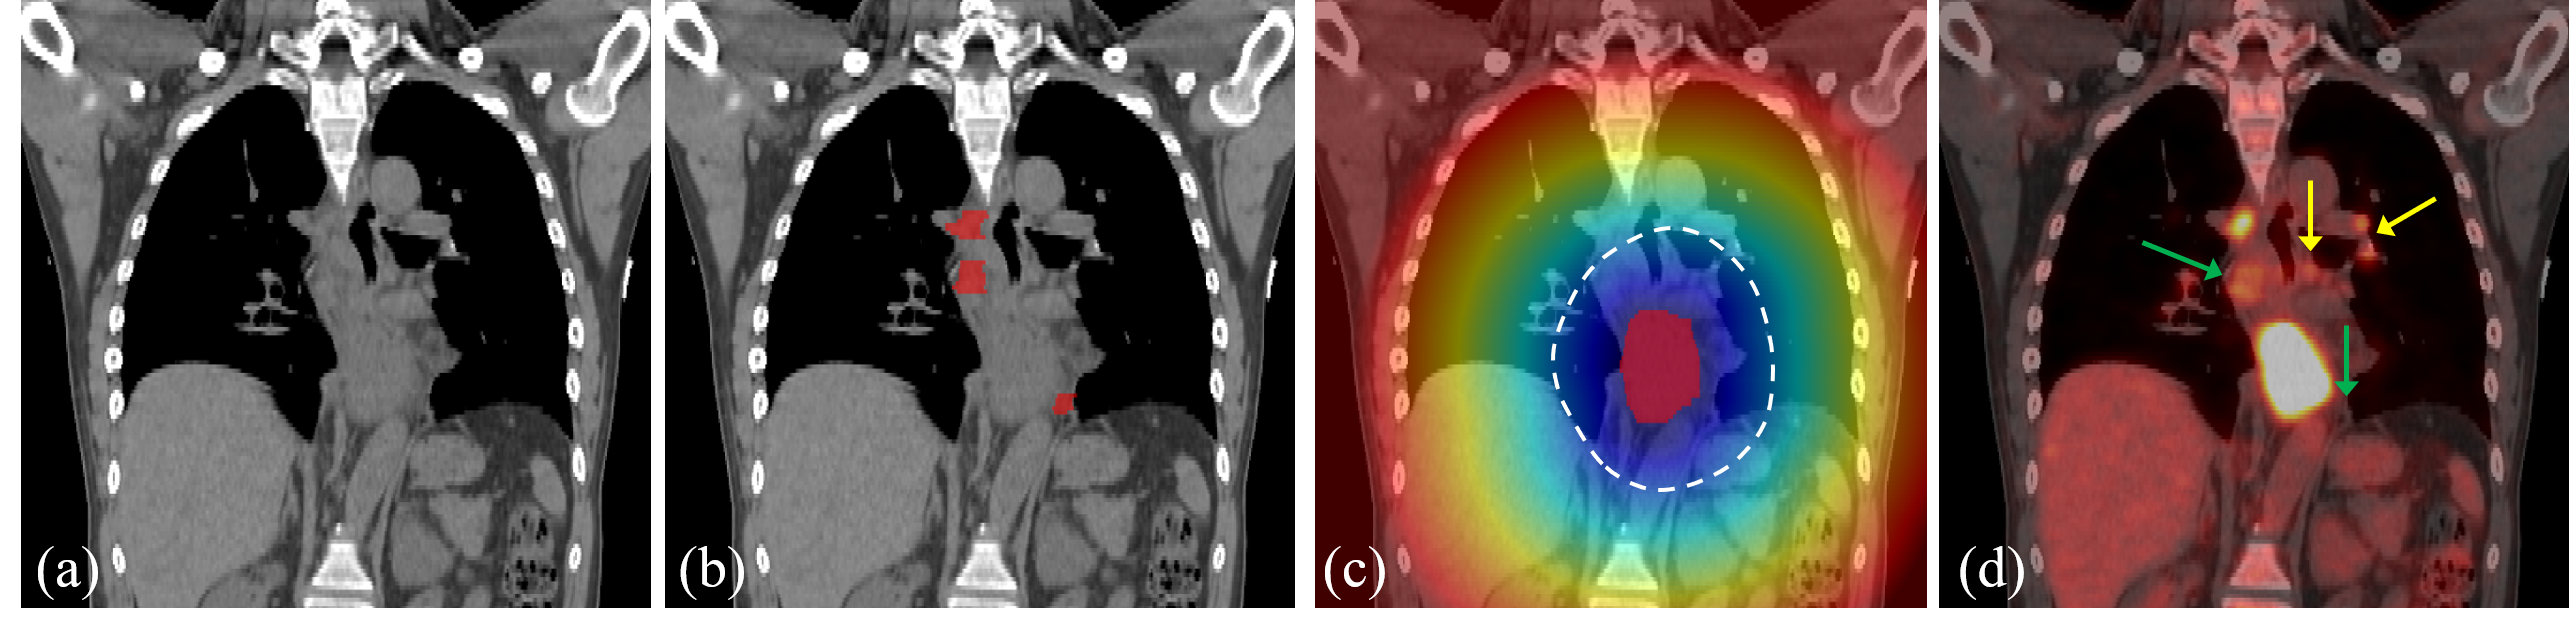

Refer to caption

Figure 2: (a) A coronal view of RTCT for an esophageal cancer patient. (b) The manual annotated OSLN mask. (c) Tumor distance transform map overlaid on RTCT. The primary tumor is indicated by red mask in the center and the white dash line shows an example of the tumor proximal and distal region division. (d) PET imaging overlaid on RTCT. The yellow arrows show several FP PET signals, and the green arrows indicate two FN OSLNs where PET has weak or even no signals. A big central bright region in PET is the primary tumor region.

Current clinical practices offer valuable insight in how to tackle this problem. For instance, physicians condition their analysis of suspicious areas based on their distance to the primary tumor. For LNs proximal to the tumor, physicians will more readily identify them as OSLNs for the radiotherapy treatment. However, for LNs far away from the tumor, physicians are more discriminating, only including them if there are clear signs of metastasis, such as enlarged in size, increased PET signals, and/or other CT-based evidence [29]. Hence, distance to the primary tumor plays a key role in physician’s decision making. Besides the distance, the PET modality is also highly important, as it significantly increases sensitivity [9]. However, PET is noisy and increased PET signals can often associate to normal physiological uptake. Moreover, PET only highlights 33%similar-toabsentpercent33\sim 33\% of the OSLNs [18]. This is demonstrated in Fig. 2(d)’s example, where PET provides key information in identifying OSLNs, which might be too difficult to detect from RTCT only. Yet, the PET also exhibits false positives (FPs) and false negatives (FNs). Based on this observation, an effective method to leverage the complementary information in RTCT and PET is crucial, but this must be done with care.